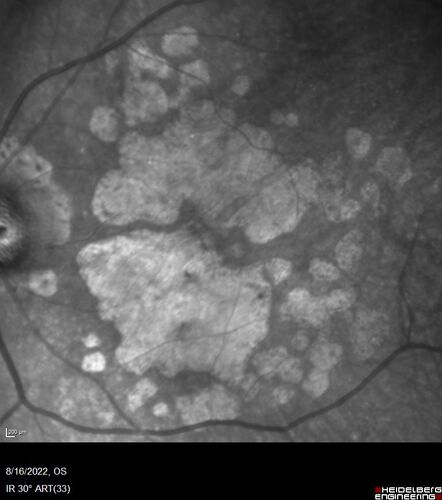

Optic Disc Melanocytoma - Atypical

45 year old female with normal vision and optic nerve lesion in the left eye. VA 20/16 OU. Extensive testing was normal including brain and orbit MRI. The lesion has been stable for 5 years.

AMD End stage both eyes - scar OD - GA OS